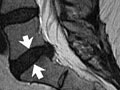

La imagen es cortesía de Intermountain Medical Imaging, Boise, Idaho. Todos los derechos reservados.

Una vista lateral de la columna lumbar muestra discos, conducto vertebral y raíces nerviosas normales (ver figura 1). Las raíces nerviosas normalmente flotan en el conducto lleno de líquido. La figura 2 muestra una pequeña hernia de disco que sobresale en el conducto en dirección a las raíces nerviosas.